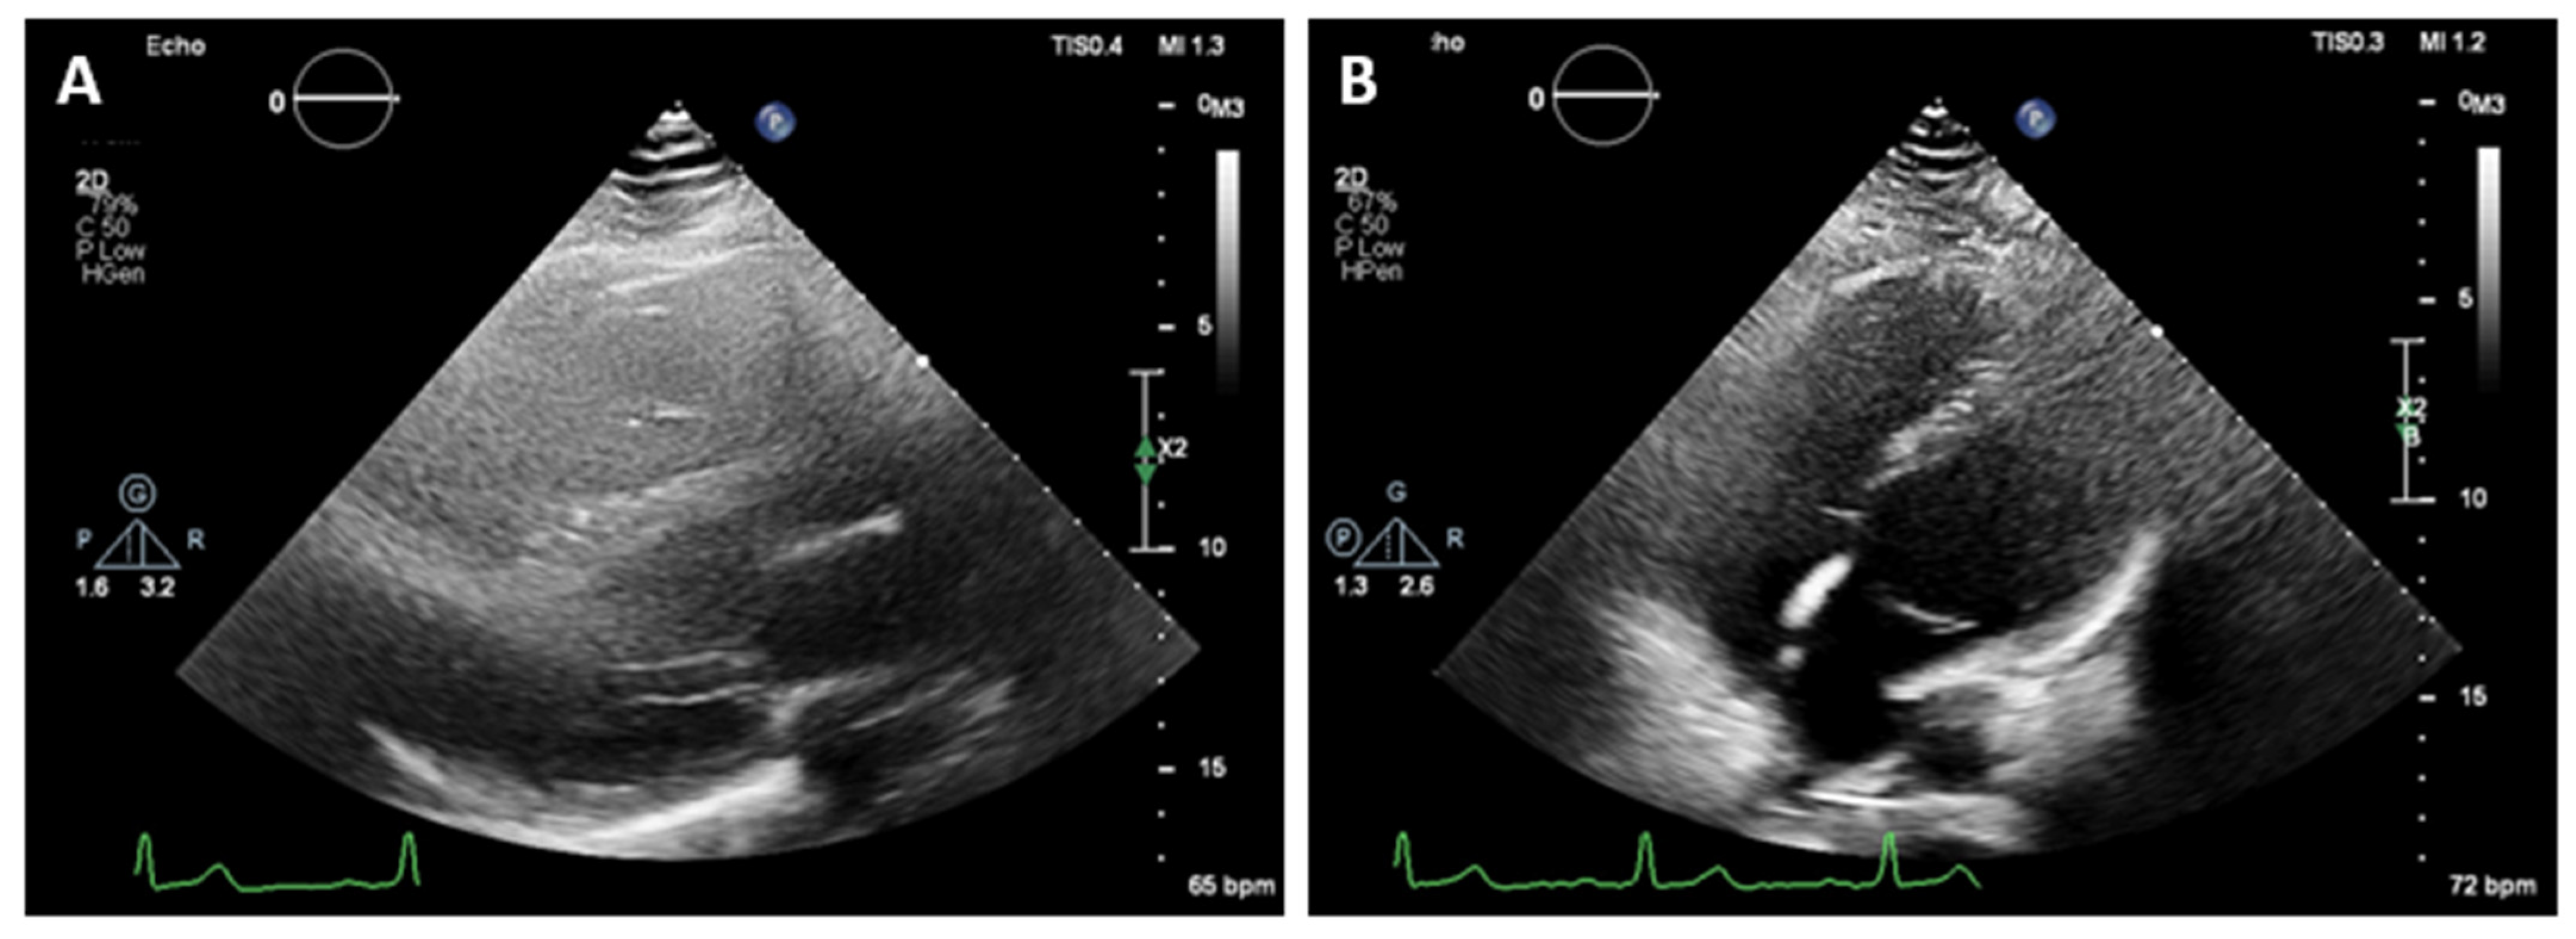

The CMR confirmed the abnormal position of the heart in the left hemithorax with laterally and posteriorly displaced apex and interposition of the lung tissue between the aorta and pulmonary trunk. There was no detectable pericardium overlying the left ventricular wall, and only a small discontinuous segments of pericardium were visualized surrounding the right atrium and right ventricular lateral wall (Figure 3 and Figure 4). Biventricular volumes and function were in the reference range. Additionally, a patent foramen ovale was visualized with no significant left-to-right shunt (Qp/Qs = 1.1).

Figure 4. SSFP CINE image in four chamber view (A) and T1-weighted fast spin-echo in axial view (B) demonstrate discontinuous segments of pericardium surrounding the right atrium and right ventricular lateral wall. No detectable pericardium was found around the left ventricular wall.